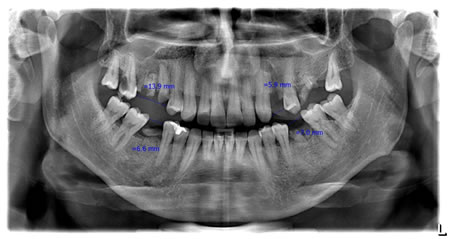

Aşağıda Standart Panoramik Röntgen ve Aproksimal Panoramik Röntgen görüntüleriyle ilgili örnekleri görebilirsiniz.

4.2 Aproksimal Panoramik Röntgende Ölçümler